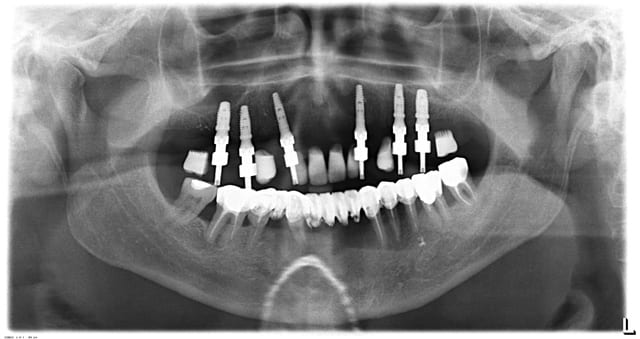

ci joint les panos du cas

j'envoie une ou 2 photos de la proth

des que j'ai 5 min

Pilo 01 qu2ktm - Eugenol

Pilo2 qjmjii - Eugenol

C'est lesquels que tu as perdu ?

De 16 a 23

je trouvais les axes et la répartition êtes forcés plutôt bonne

La paro en bas est comment ?

J'aurais viré quelques dents avant de poser des implants, cette bouche ne m'a pas l'air très saine...